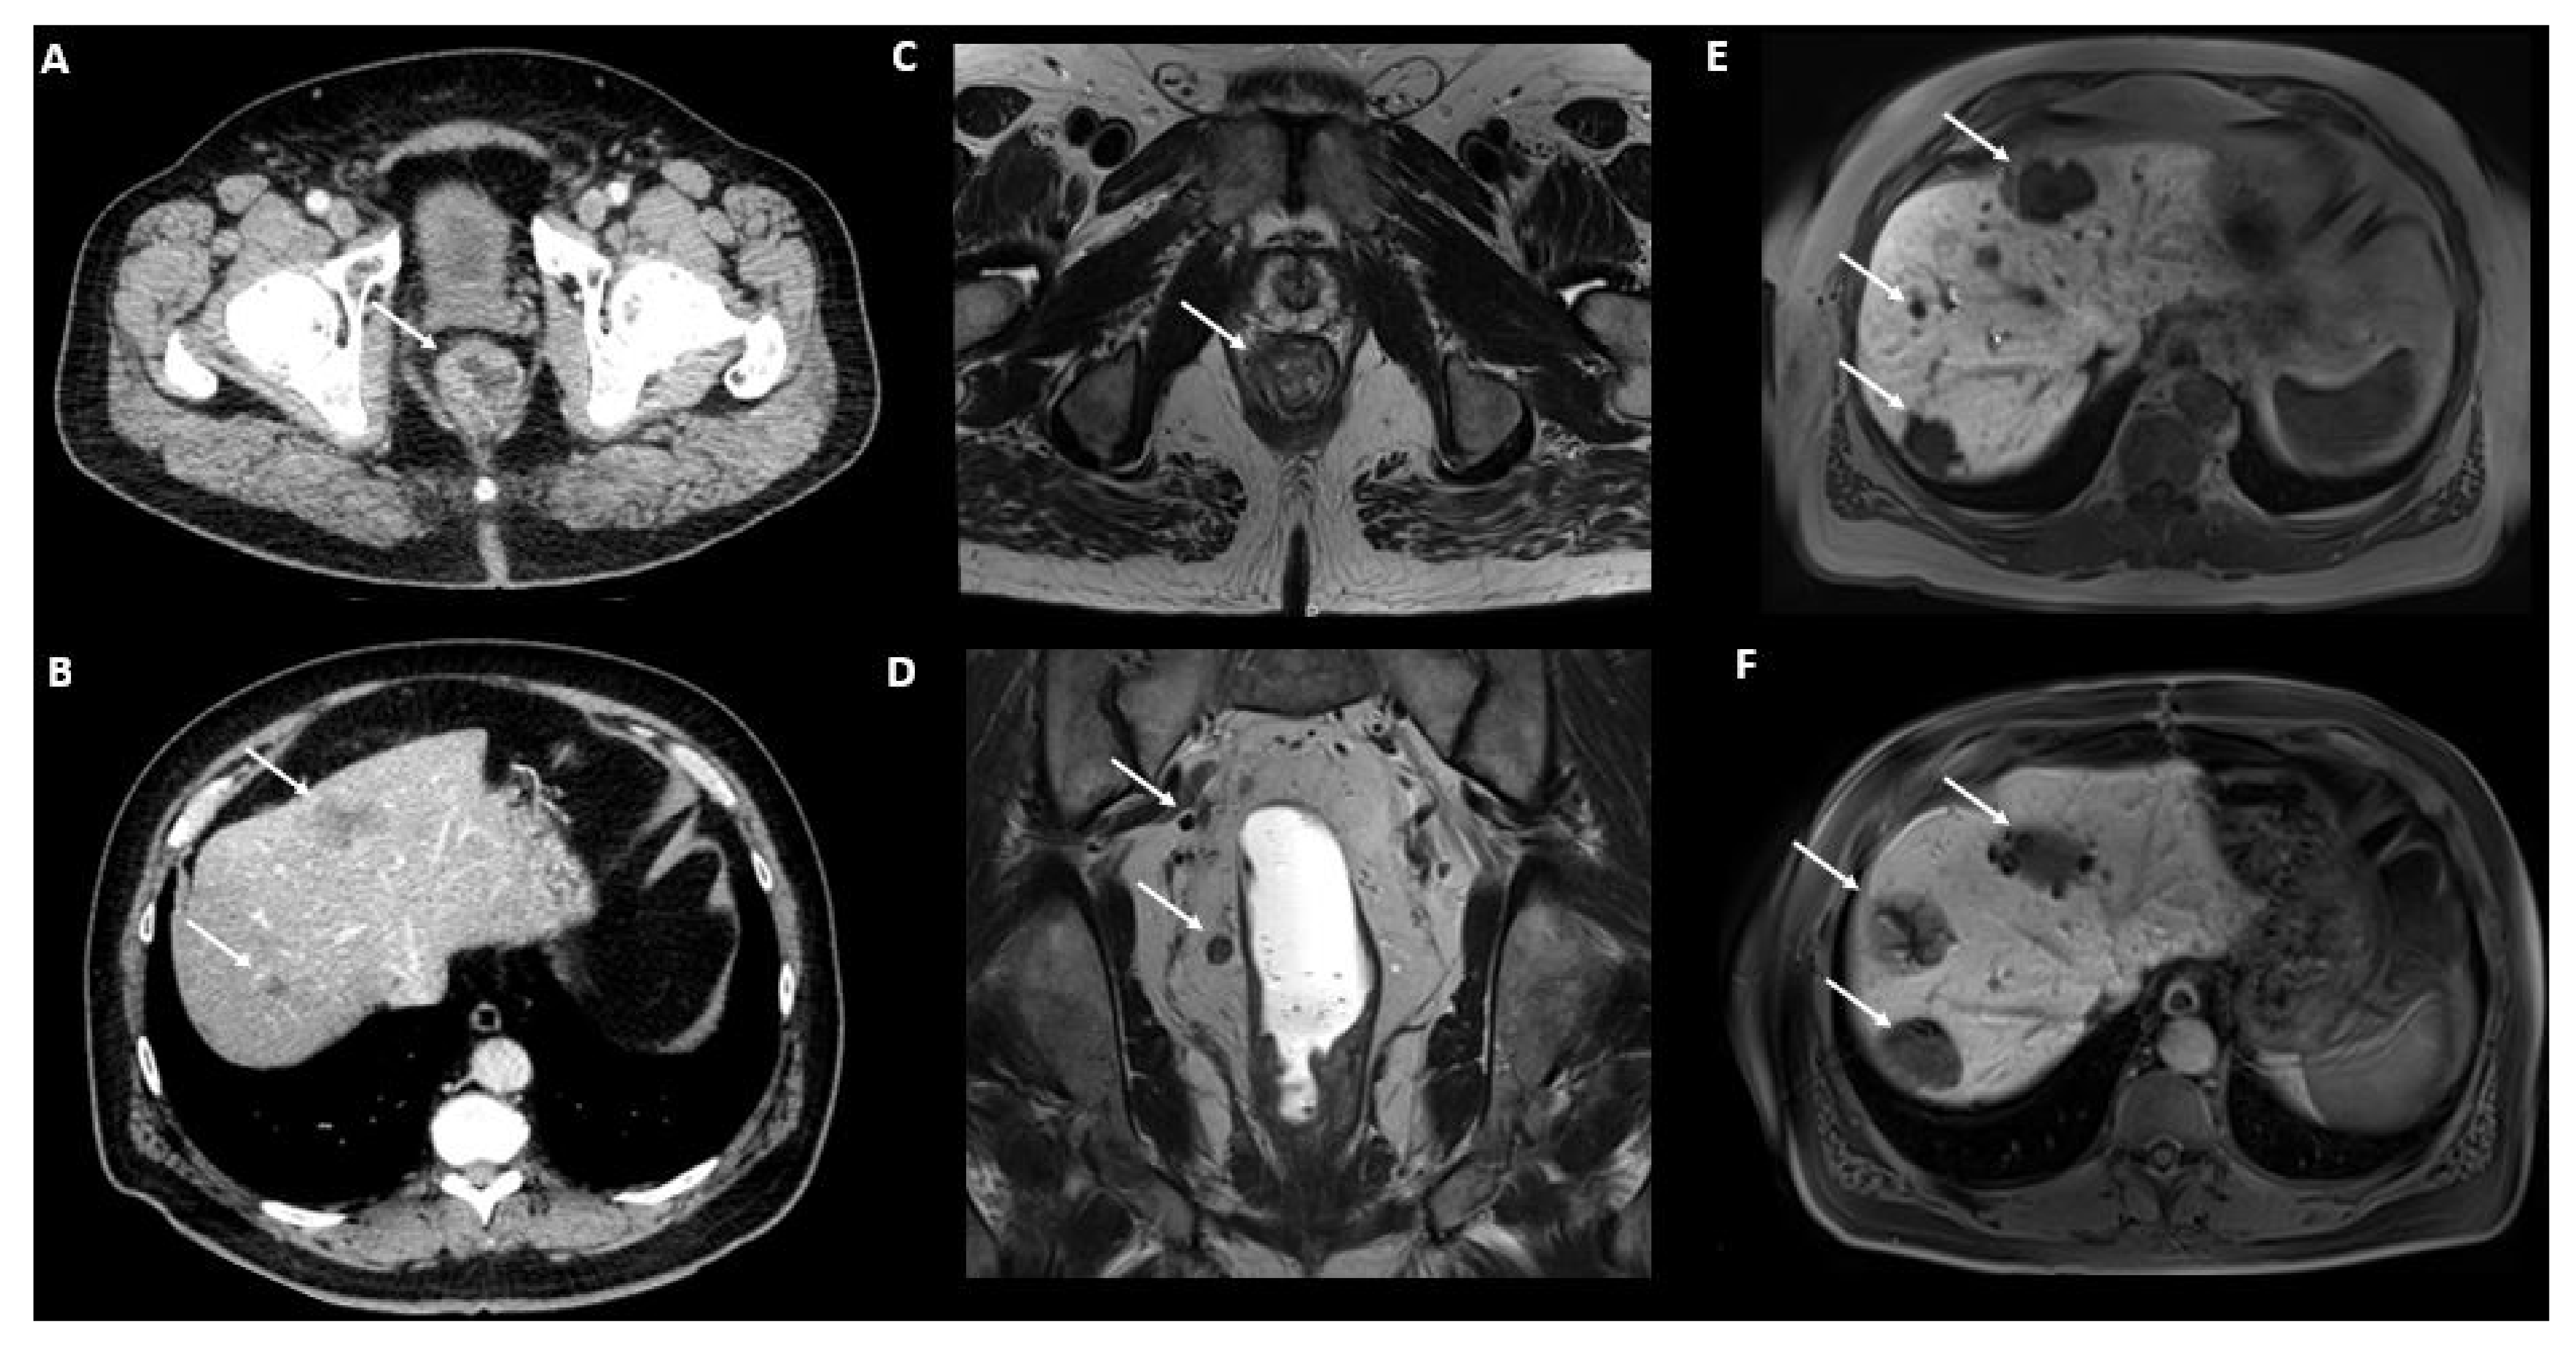

2.5.2. Magnetic Resonance Imaging (MRI)

2.5.3. Metabolic and Receptor-Specific Imaging

2.5.4. Combined Modalities